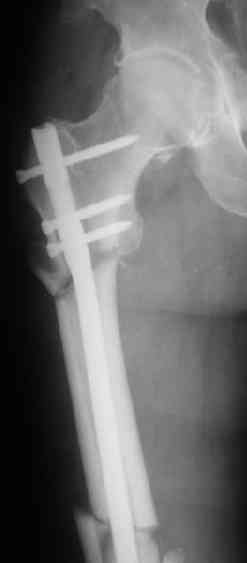

СМ> Если имеются под рукой Р-снимки, продемонстрируйте, плиз.

Вот несколько. С тисками и трубой на днях сделаем.

Гвозди с латерализованным проксимальным концом сейчас становится мэйнстримом, поскольку трохантерная точка входа во всех отношениях

благоприятнее f. piriformis.

Моделирование титановых заготовок, в том числе трубой в тисках, при остеосинтезе по Звереву-Ключевскому - тоже широко распространенная

практика, и бедренные гвозди там тоже достаточно мощные...